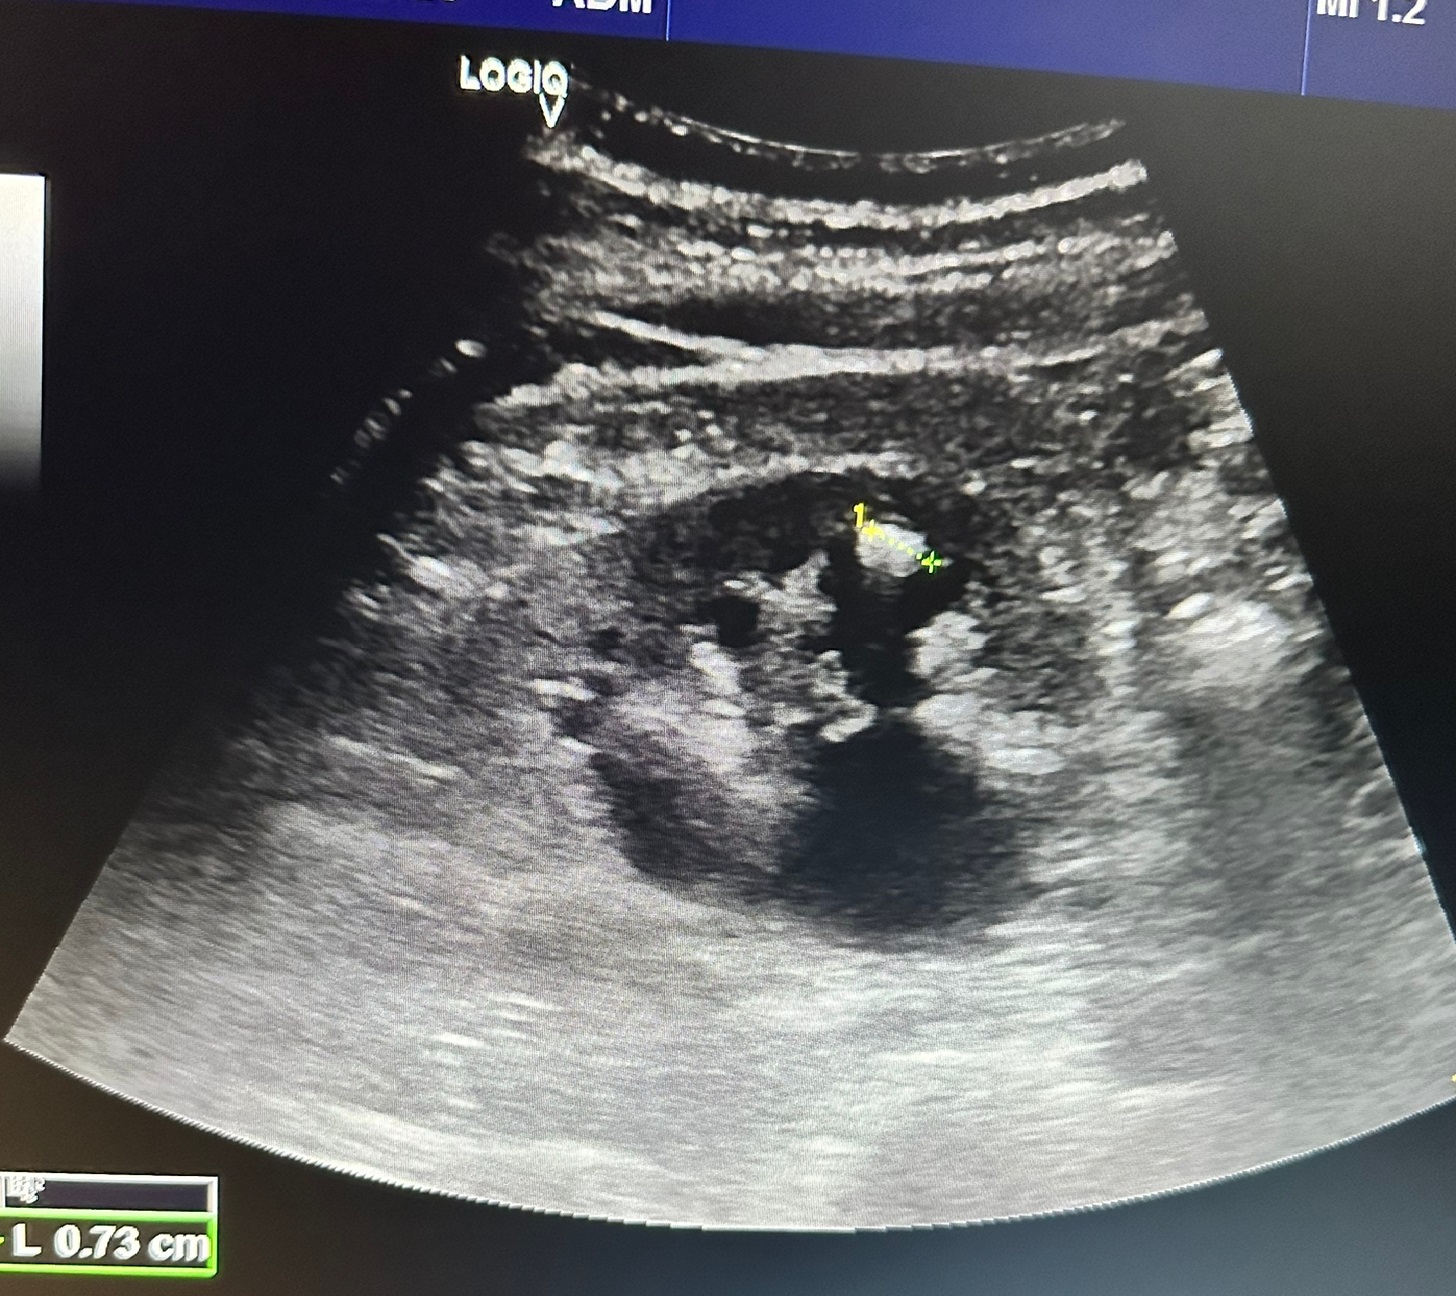

Hallazgos ecográficos

En la valoración se observa riñón derecho con marcada hidronefrosis grado 3, observándose pelvis renal grande, calices dilatados y parenquima normal. Presenta una litiasis de 0,73 cm en el polo inferior del riñon derecho.